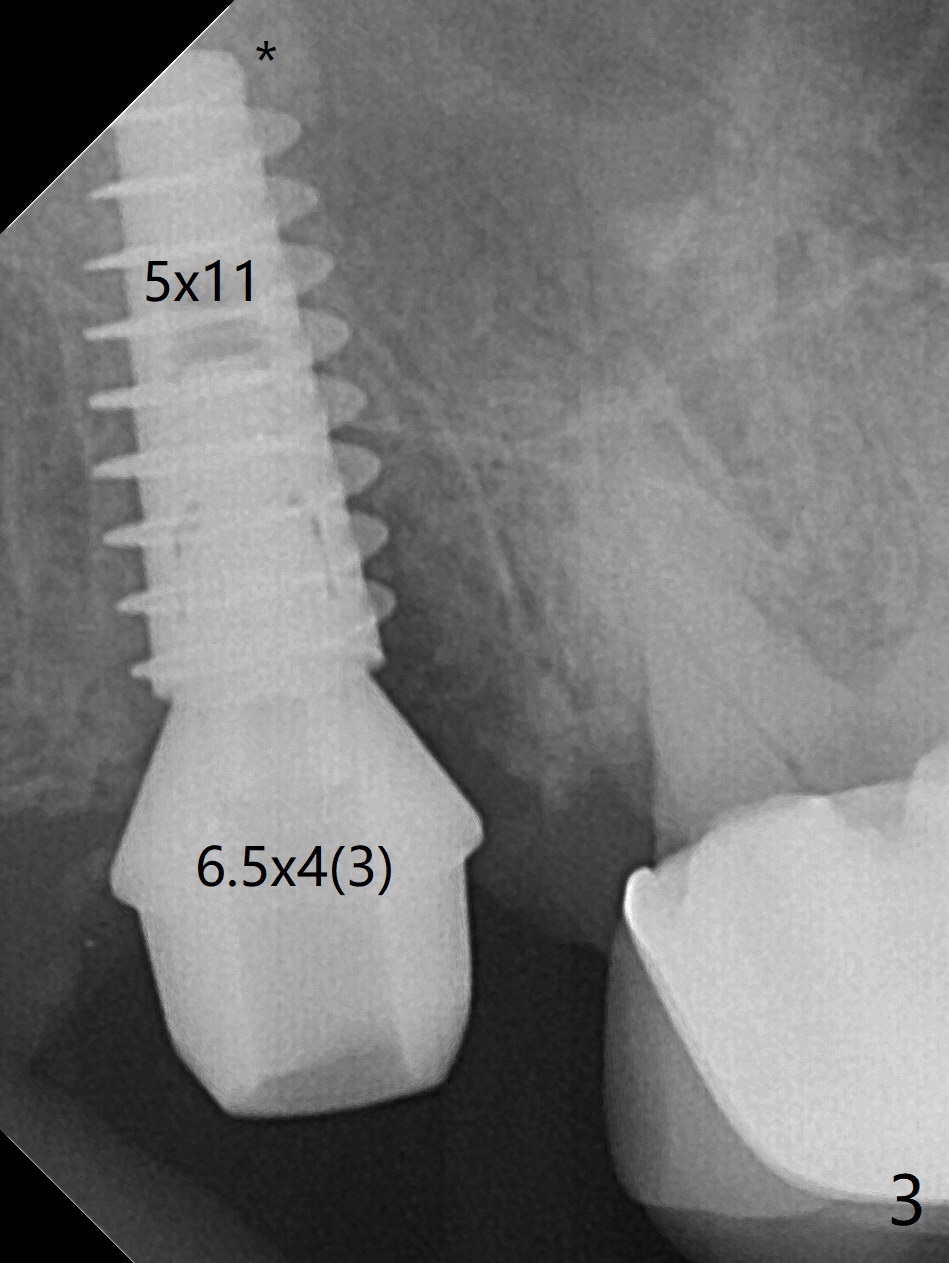

When the tooth #2 is extracted, there is sinus perforation in the palatal apex, consistent with preop CT (Fig.1: P). There is no bone shaving associated with drill sequence in the buccal socket (until 3.5x8.5 mm). With sticky bone and 4.5x10 mm IS dummy implant, sinus lift does not happen. Sinus floor perforation is felt when a 2.2x10 mm drill is used slowly. But air leaks from the palatal socket. With bone graft, a 4x10 mm dummy implant lifts the sinus (Fig.2). After further graft and 4.5x10 mm dummy implant, a 5x11 mm final implant is placed with 15 Ncm with sinus lift (Fig.3,4 *). Following abutment insertion, sticky bone is packed around the implant and abutment (Fig.5,6 S). Prior to final implant placement, a small piece of PRF and collagen and Osteogen Plugs are placed in the palatal socket for repair. Before discharge, there is mild nasal hemorrhage.